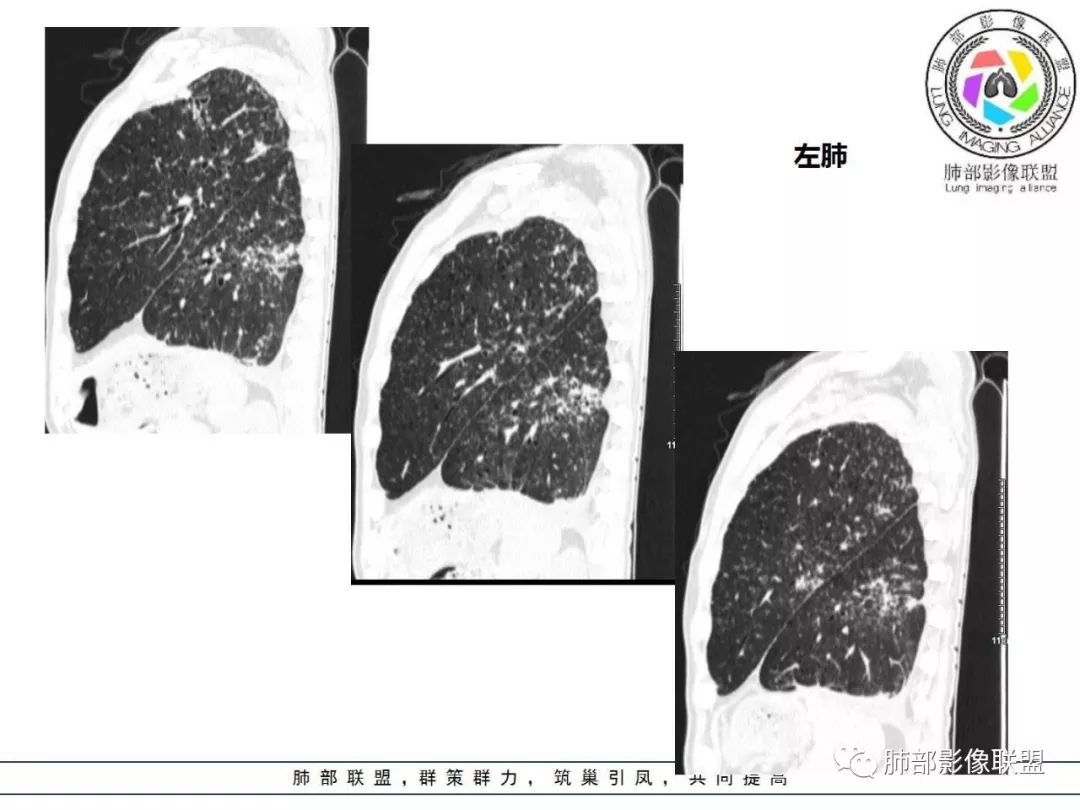

双肺间质性病变,中央间质增厚,胸膜下间质增厚,左侧胸膜肥厚,胸廓变小,肋间隙变窄。

胸部CT:两肺弥漫病灶,磨玻璃影,少许实变,部分累及胸膜,磨玻璃区可见囊?少许胸腔积液,两肺可见结节,支气管血管束增粗,小叶间隔增厚,支气管走形有扭曲扩张,可见纤维化。气肿、大泡。考虑:感染性病变,PCP?查下HIV,CD4,G等。鉴别结核、结缔组织病肺浸润。

中年男性,亚急性起病,发热,咳嗽,黄痰,具体治疗不详,CRP增高,余感染指标及特异性指标不详,基础疾病不详,胸部CT提示双肺散在索条影,右肺为重,胸膜下及中央间质分布为主,磨玻璃影,牵拉性支扩,实变,有囊,LIP合并感染。

胸部CT:两肺弥漫病灶,中央间质分布为主,部分位于胸膜及叶间裂旁,磨玻璃影,斑片影,部分实性结节,肺气囊,支气管血管束增粗,小叶间隔增厚,叶间裂不均匀增厚,支气管走形有扭曲扩张,可见纤维化、气肿、大泡。考虑:LIP加MALT。鉴别PLCH、PCP、结核、结缔组织病肺浸润。

双肺弥漫性病变,多发磨玻璃密度及小叶间隔增厚,大部分沿支气管血管束分布,伴支气管轻度扩张,以午后及晚上发热为主,考虑感染性病变,间质性结核可能大,另双肺多发肺气囊,LIP待排

病灶呈片状磨玻璃密度影,呈典型的烟花征。磨玻璃影密度偏高,有网结节样改变,与正常肺实质分界清楚,且常见相对高密度的勾画。

病变一般沿血管支气管束分布或小叶分布,一般上肺多于下肺(这与常见继发性肺结核分布相若)。

2. 肺气肿背景(小叶中心性肺气肿);双肺多发病灶整体沿血管支气管束及胸膜下分布,以上叶及下叶背段分布为主,有实变及GGO,边界清楚,有树芽,小叶间隔及中央间质增厚,叶间裂见到多发结节,部分支气管不规则牵拉扩张,提示病灶纤维化明显,结合临床病史,考虑病灶为间质性感染,肺门及纵隔内有钙化淋巴结,小叶间隔结节,考虑淋巴道增值性疾病可能,综合常规要怀疑间质性肺结核。